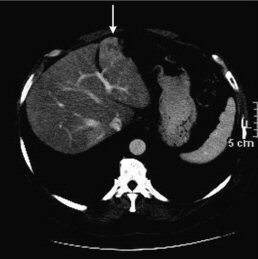

| The diagnostic CT image (top) shows a patient with colorectal cancer with hepatic metastasis in the left hepatic lobe (arrow), but it is not on PET/CT (above). The corresponding PET image (below) confirms metastasis. The study notes that treatment was not changed, as it was seen by PET scan. "Limitations of CT during PET/CT" (Journal of Nuclear Medicine, Vol. 48:10, pp. 1583-1591). Reprinted by permission of SNM. |

The discrepancy due to the lack of intravenous contrast material "most often led to undetected liver metastases or poor lymph node recognition, and most often was apparent in patients who were likely to have liver metastases and undergo PET/CT -- that is, patients with colorectal cancer," the researchers wrote.

In addition, they noted that some metastases could be seen on PET/CT "if a wide window/level was applied to the CT image or if the metastases were large or metabolically active enough to be seen on PET."